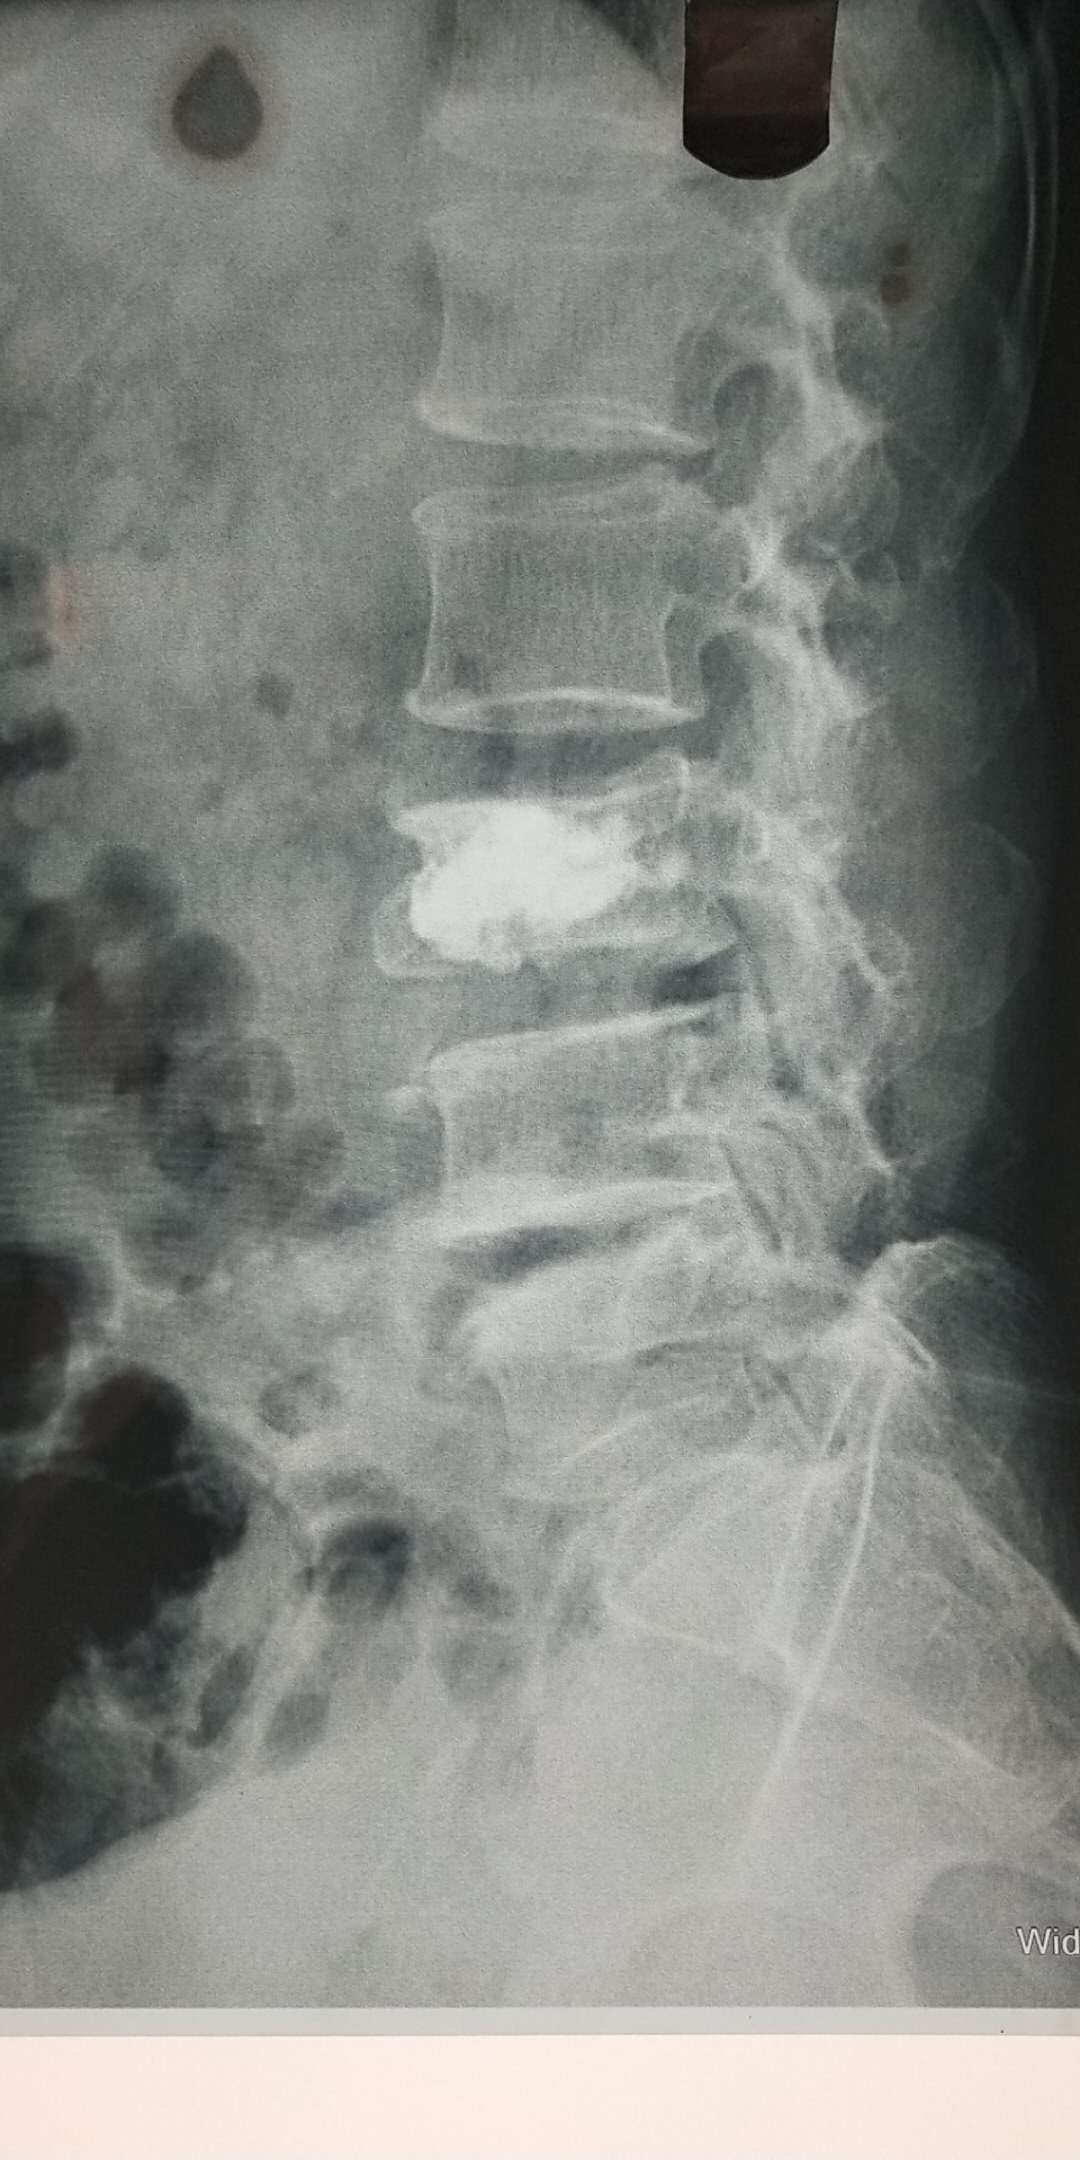

術(shù)前片子

骨一科已成功為數十名患者成功開(kāi)展PVP手術(shù)。僅今年3月份,在何光亮主任的帶領(lǐng)下,骨一科已經(jīng)成功開(kāi)展5例PVP手術(shù),術(shù)后患者相當滿(mǎn)意,全部患者術(shù)后可自行行走,擺脫臥床。3月21日患者王某,90歲,因摔傷致腰部疼痛3天為主訴入院,診斷腰1椎體骨折、骨質(zhì)疏松癥、高血壓等,住院后經(jīng)過(guò)科室術(shù)前討論,何主任為患者制定了PVP手術(shù)方案,于3月22日在行腰1椎體壓縮性骨折經(jīng)皮穿刺椎體成形骨水泥填充術(shù),術(shù)后24小時(shí)患者即下床活動(dòng),術(shù)后一周患者痊愈出院,隨訪(fǎng)患者已基本恢復到術(shù)前狀態(tài)。